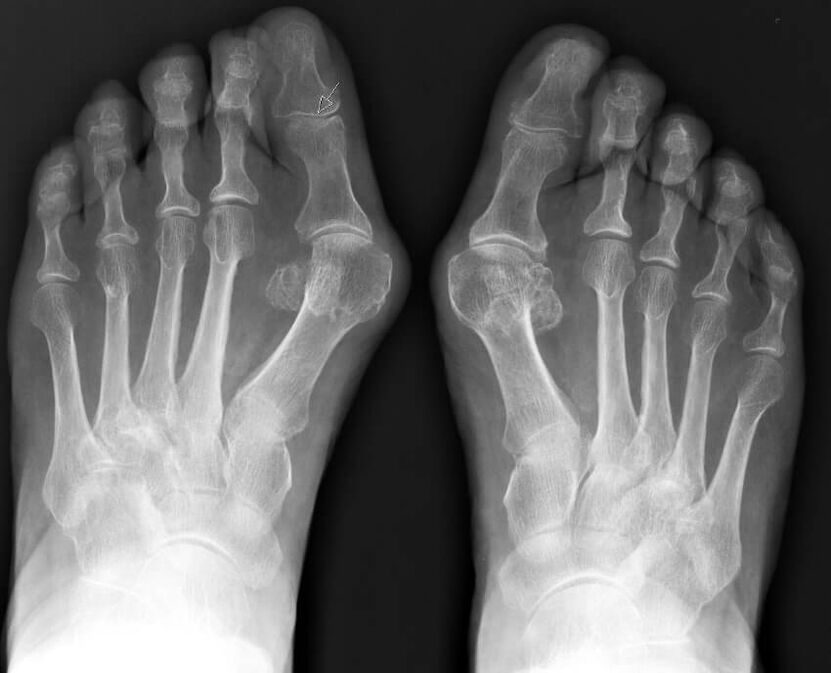

To je bolest kod koje se nožni palac pomiče u stranu i pojavljuje se kost u području metatarzofalangealnog zgloba. Šifra patologije za hallux valgus prema ICD 10 je M20.1.

Glavna metoda za određivanje stupnja patologije je x-zrake, koje se uzimaju u dvije projekcije s opterećenjem. Osim toga, liječnik može propisati plantografiju, CT, MRI i druge studije.